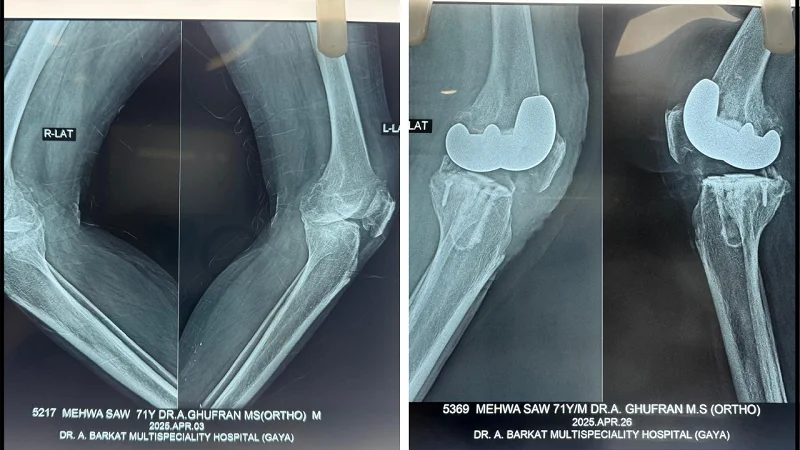

Dr. A Ghufran, MBBS, MS (Ortho) leads the orthopedic department at Dr. A. Barkat Multispeciality Hospital as our head orthopedic specialist and knee replacement surgeon in Gaya. Dr. Ghufran has performed numerous knee replacement surgeries and has extensive medical expertise and specialized training in the field.

Our hospital uses state-of-the-art surgical tools, advanced imaging technology, and up-to-date monitoring systems to achieve the best possible results. As the best orthopedic in Gaya, Dr. A Ghufran combines technical expertise with compassionate care, providing personalized attention and highest quality treatment to his patients.